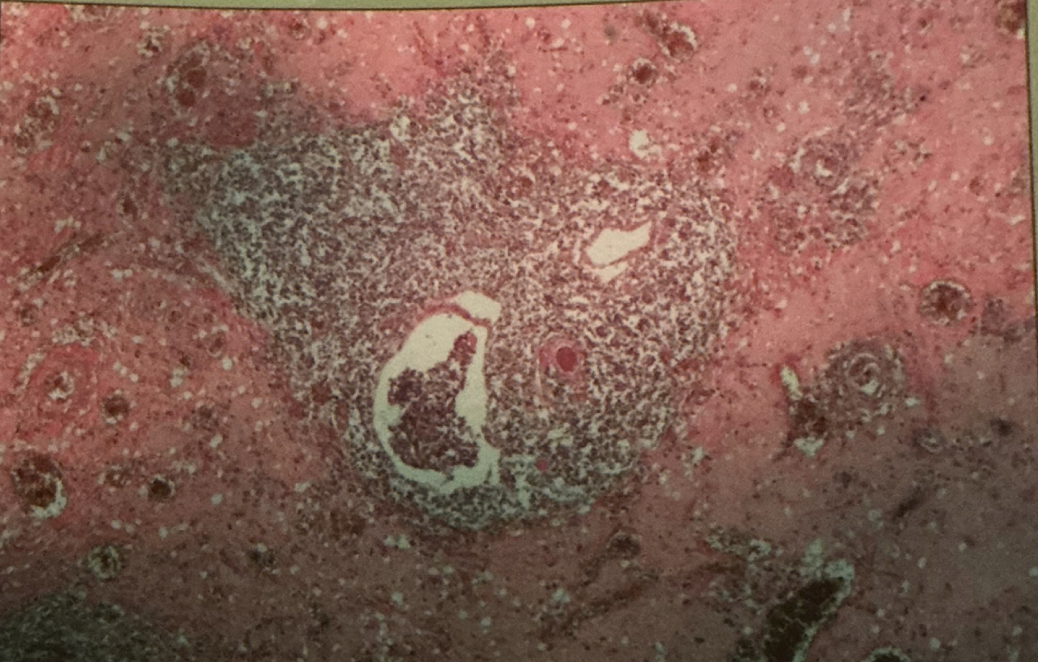

lymph node

hodgkin’s granuloma

hodgkin’s granuloma

cancer of lymph system - breakdown of red and white pulp

reed-sternberg cells

derived from B lymphocytes